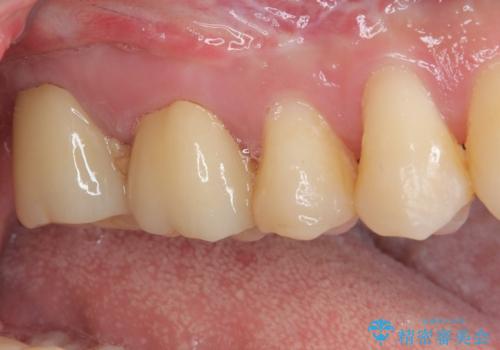

下顎大臼歯は根管治療がされている歯が咬合時に痛みを感じ、上顎の大臼歯2歯は冷たいものがしみる状態でした。

まずはしみる上顎の歯を仮歯に置き換え、その後下顎の根管治療を行った上で、異常が認められなければオールセラミッククラウンにて補綴治療を行うこととしました。

上顎は仮歯に置き換えた後に、それまでの痛みは一切感じなくなり、下顎も一度目の根管治療で痛みを感じることはなくなりました。